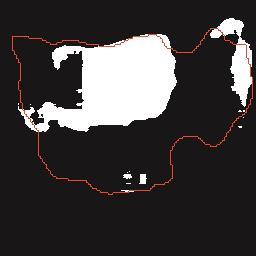

乳腺癌是全球女性最常见的恶性肿瘤之一,准确的病变分割对于乳腺癌的早期诊断与治疗具有重要意义。然而,由于病变形态的多样性以及超声成像机制的复杂性,现有基于深度学习的乳腺超声图像病变分割方法在分割准确性方面仍面临巨大挑战。为进一步提升乳腺超声图像中病变区域的分割精度,该文基于经典U-Net架构,提出了一种新型乳腺超声图像病变分割网络(CWSASKM-BBAM-Net)。首先,在网络中引入逐通道空间自适应选择核卷积模块(CWSASKM),根据不同通道的语义特征为每个空间位置自适应选择感受野大小,以增强多尺度信息的建模能力;然后,引入双向边界感知机制(BBAM),通过融合正向与反向注意力,对目标显著区域及其边界进行协同建模,同时逐步提升对非显著区域与病变区域的区分能力,以进一步强化边界信息的表达;最后,在3组公开乳腺超声图像数据集(BUSI、UDIAT和STU)上开展分割实验。结果表明:该方法在数据集BUSI上的杰卡德指数、精确率、召回率和Dice相似系数分别为71.97%、82.85%、81.40%和80.44%,较次优方法分别提升1.69、1.05、1.28和1.84个百分点;在数据集UDIAT上,这4项指标分别达到78.14%、88.31%、86.73%和86.10%,较次优方法分别提升了2.75、2.04、0.56和2.01个百分点;在外部数据集STU上,该方法也取得了优于其他方法的整体表现。实验结果表明,CWSASKM-BBAM-Net在乳腺超声图像分割任务中展现出更优的整体性能。